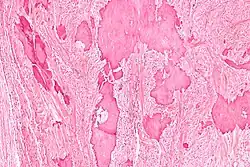

| Low magnification micrograph of a calcified ovarian fibroma in the context of nevoid basal cell carcinoma syndrome. H&E stain. | |

On gross pathology, they are firm and white or tan. On microscopic examination, there are intersecting bundles of spindle cells producing collagen.

There may be thecomatous areas (fibrothecoma). The presence of an ovarian fibroma can cause ovarian torsion in some cases.